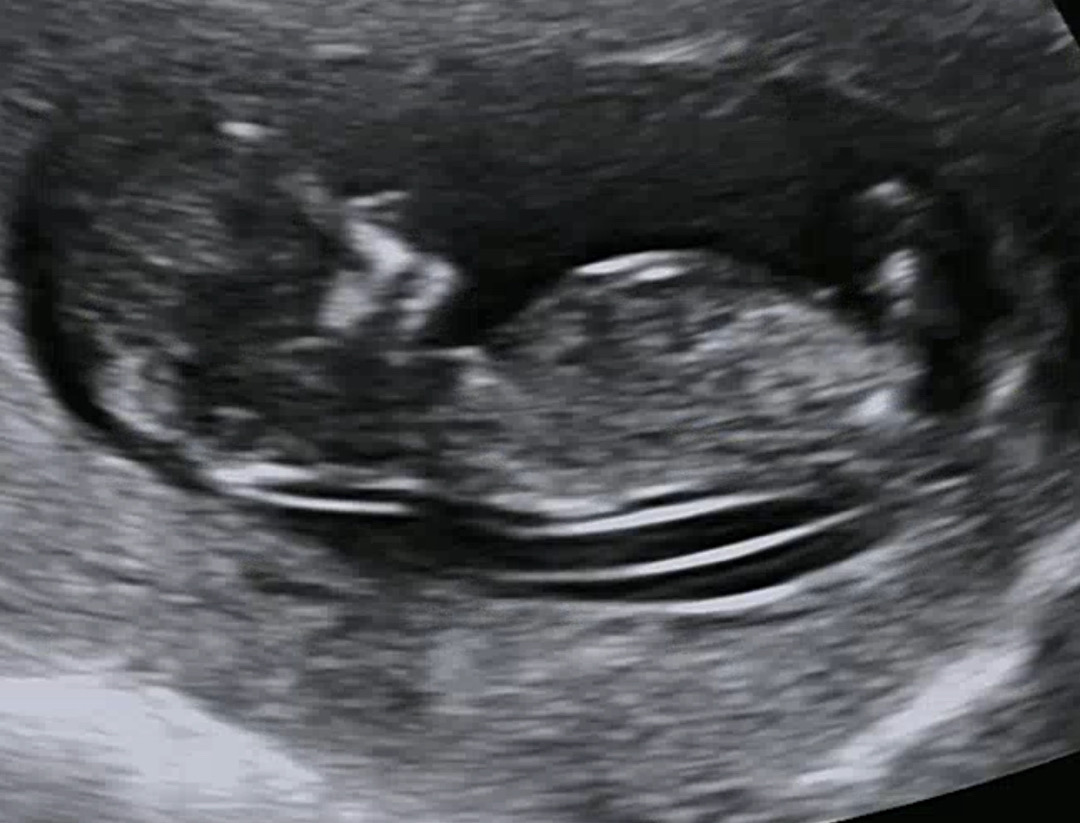

1차 기형아검사!

이제 병원까지 한달 남았어요 ㅠㅠㅠ언제 기다리죠 11주인데 혹시 저때는 생식기가 안보이는건가요??

각도법으로 보시면되는데..동영상있으면 생식기 부위가 조금 더 명확하게 나온걸로 보셔야할거같아요

11주인데 1차 기형아 검사 하셨네요~ 제가 본게 맞는지는 모르겠지만 그게 맞다면 각도법으론 딸 같아 보여요ㅎㅎ

감사합니다 ㅎㅎㅎㅎ 저도 느낌상은 딸 같아요 ㅎㅎㅎㅎ